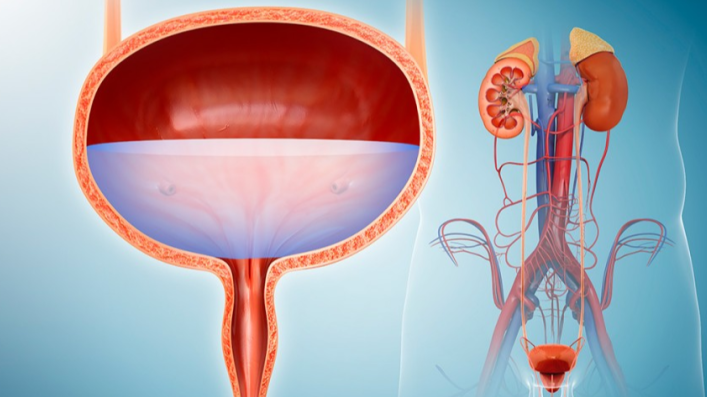

Swaran multispecialty hospital is a premier multi-specialty healthcare service provider in North India.In the journey of 30+ years, we’ve reached the unreached, cared the uncared and touched the untouched and won innumerable hearts.

- ICU and medical facilities.

- We Care for our Patients.

- Your Health is our priority.